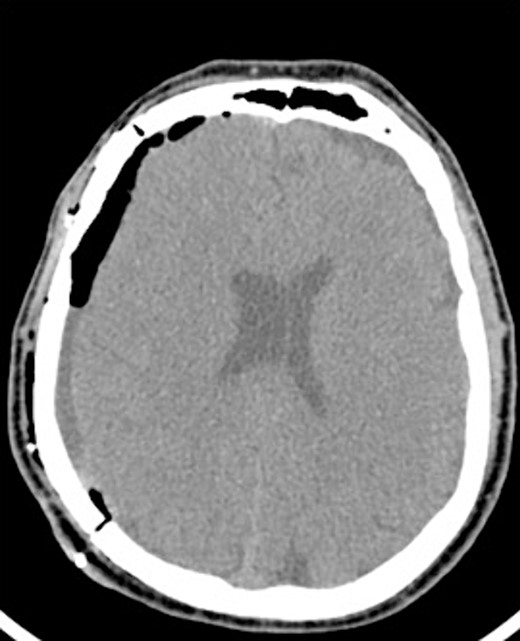

An AR system was used to register the patient’s 3D anatomy onto the patients’ head (Fig. 2). Burr hole locations were annotated onto the registered 3D model to assist with craniotomy planning. Visualization of the 3D model confirmed plans for safe burr hole placement away from the dural venous and bony sinuses for a right frontoparietotemporal craniotomy. The AR headset was used once again to visualize the hematoma, vascular structures, and to confirm proper burr hole locations. The evacuation of the subdural hematoma was performed. Eight burr holes were placed, and a 14 × 11 cm bone flap was elevated to access the dura. The dura was then opened in a curvilinear fashion and hinged over the superior sagittal sinus. The cSDH was identified by its thick parietal and visceral membranes and underlying liquefaction, and these anatomic layers correlated directly with the AR overlay. The membranes of the hematoma were resected with the cortex demonstrating no gross abnormalities. The wound was irrigated, and the dura was closed primarily. The bone flap was then secured with two central tack-up structures followed by titanium reconstruction with multiple burr hole covers. There were no intraoperative complications, and the patient tolerated the procedure well with improved strength and decreased headache postoperatively. Post-operative CT showed interval decrease in the mixed-density subdural collection and reduced midline shift (Fig. 3).